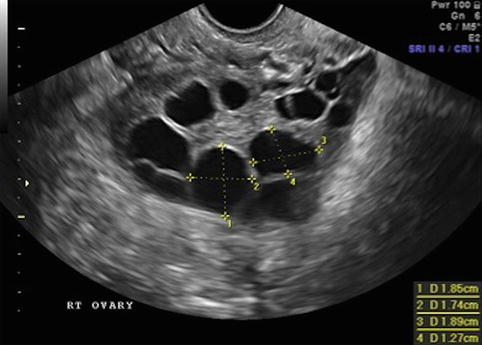

We determine that follicles of 12 19 mm on the day of trigger administration had the greatest contribution to the number of oocytes. This will have a successful ovulation. 15 10 mm and 10 9 mm and right ovary has multiple small follicles with no dominat follicle. Each additional millimeter of endometrial thickness increased the optimal follicular size by 0 5 mm.

The enlargement of the 3 to 5 mm follicle pool could be due to the atretic follicles since the number of 6 to 7 mm follicles decreased. It will then grow 2 to 3 mm in size each day. 15 11 mm and 9 10 mm follicles and right has same. Follicle sizes don t determine whether the egg is mature or not.